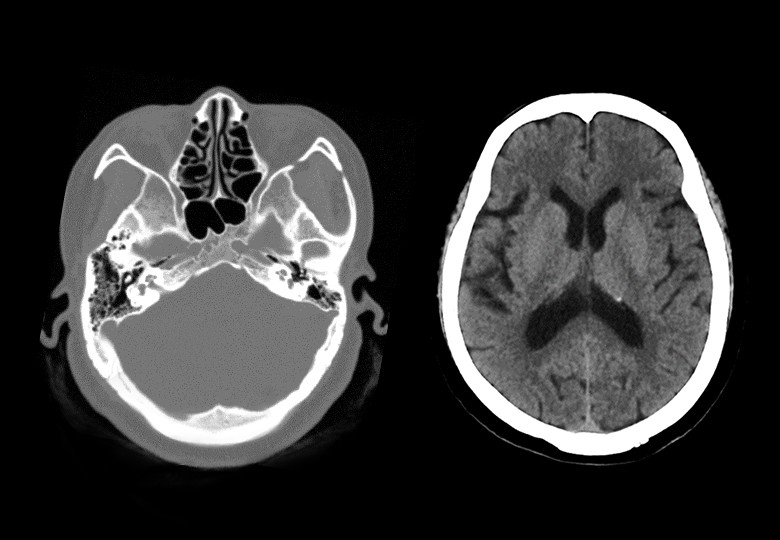

Album d'images cliniques

• Tête